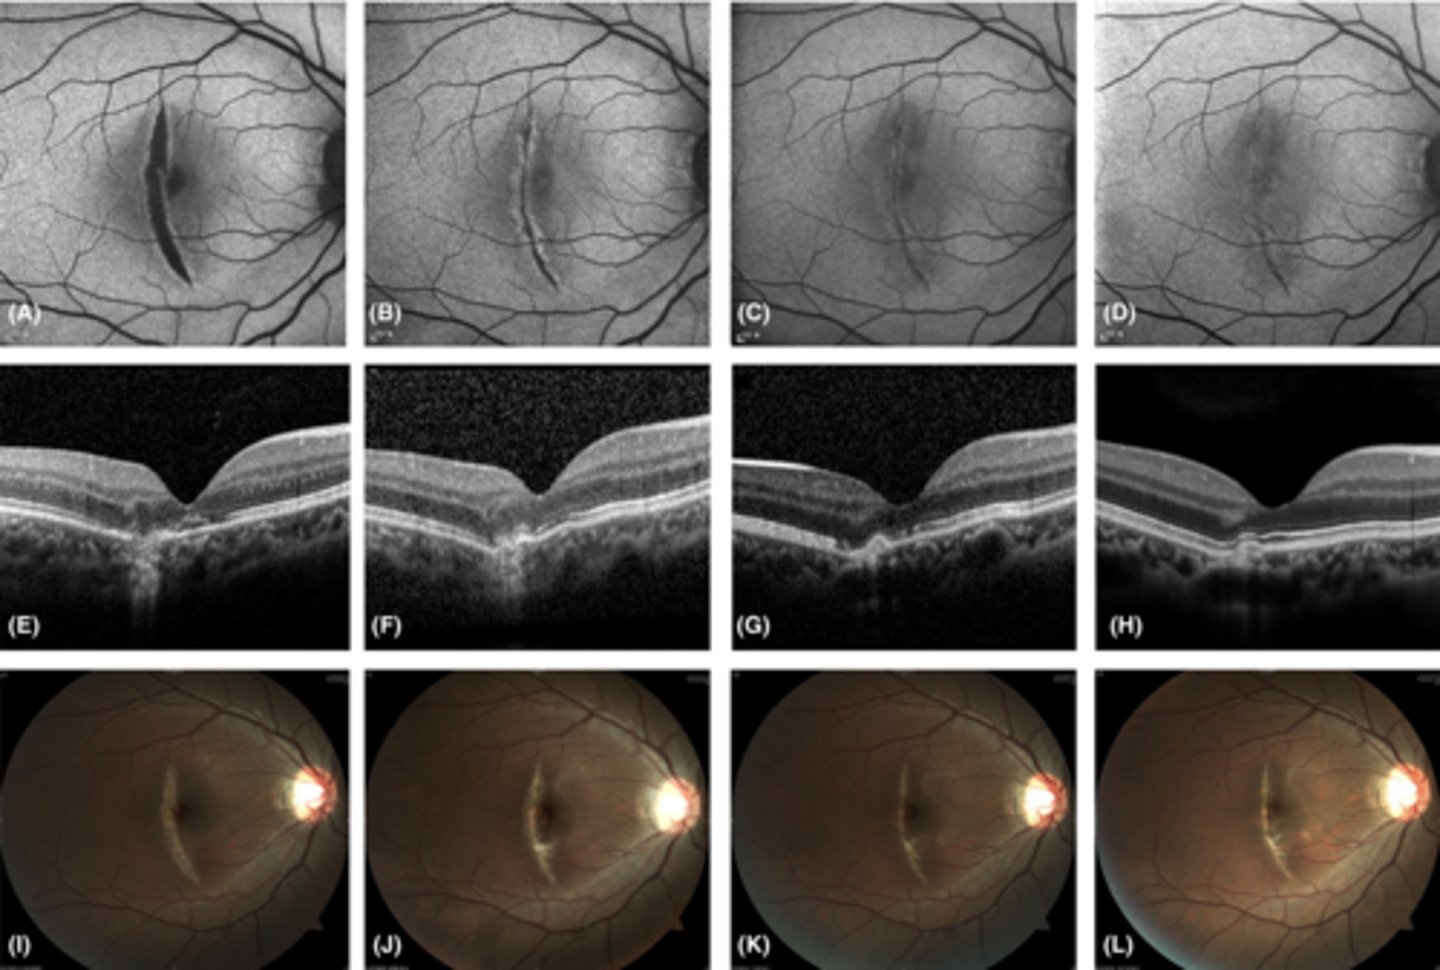

What findings of degenerative myopia are seen here?

PPA

crescent

lacquer cracks

What finding of toxoplasmosis is seen in A/B?

retinitis turns into hazy scar with nerve pallor

What finding of toxoplasmosis is seen in C/D?

scarring overtime with VA loss/scotoma

What is seen in toxoplasmosis with OCT?

acute = retinitis = inflam, thickening of layers

acute = vitritis = dots and haze vitreous

chronic = necrotizing atrophy = scarring, thinning